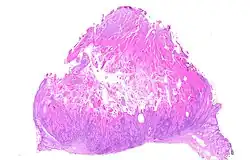

Keratoacanthoma (KA) is a common low-grade (unlikely to metastasize or invade) rapidly-growing skin tumour that is believed to originate from the hair follicle (pilosebaceous unit) and can resemble squamous cell carcinoma.[1][2]

The defining characteristic of a keratoacanthoma is that it is dome-shaped, symmetrical, surrounded by a smooth wall of inflamed skin, and capped with keratin scales and debris. It grows rapidly, reaching a large size within days or weeks, and if untreated for months will almost always starve itself of nourishment, necrose (die), slough, and heal with scarring. Keratoacanthoma is commonly found on sun-exposed skin, often face, forearms and hands.[2][3] It is rarely found at a mucocutaneous junction or on mucous membranes.[2]

Keratoacanthoma may be difficult to distinguish visually from a skin cancer.[4] Under the microscope, keratoacanthoma very closely resembles squamous cell carcinoma. In order to differentiate between the two, almost the entire structure needs to be removed and examined. While some pathologists classify keratoacanthoma as a distinct entity and not a malignancy, about 6% of clinical and histological keratoacanthomas do progress to invasive and aggressive squamous cell cancers; some pathologists may label KA as "well-differentiated squamous cell carcinoma, keratoacanthoma variant", and prompt definitive surgery may be recommended.[5][6][7][8]

Keratoacanthomas presents as a fleshy, elevated and nodular lesion with an irregular crater shape and a characteristic central hyperkeratotic core. Usually the people will notice a rapidly growing dome-shaped tumor on sun-exposed skin.[14]

If the entire lesion is removed, the pathologist will probably be able to differentiate between keratoacanthoma and squamous cell carcinoma. Follow-up would be required to monitor for recurrence of disease.[15]